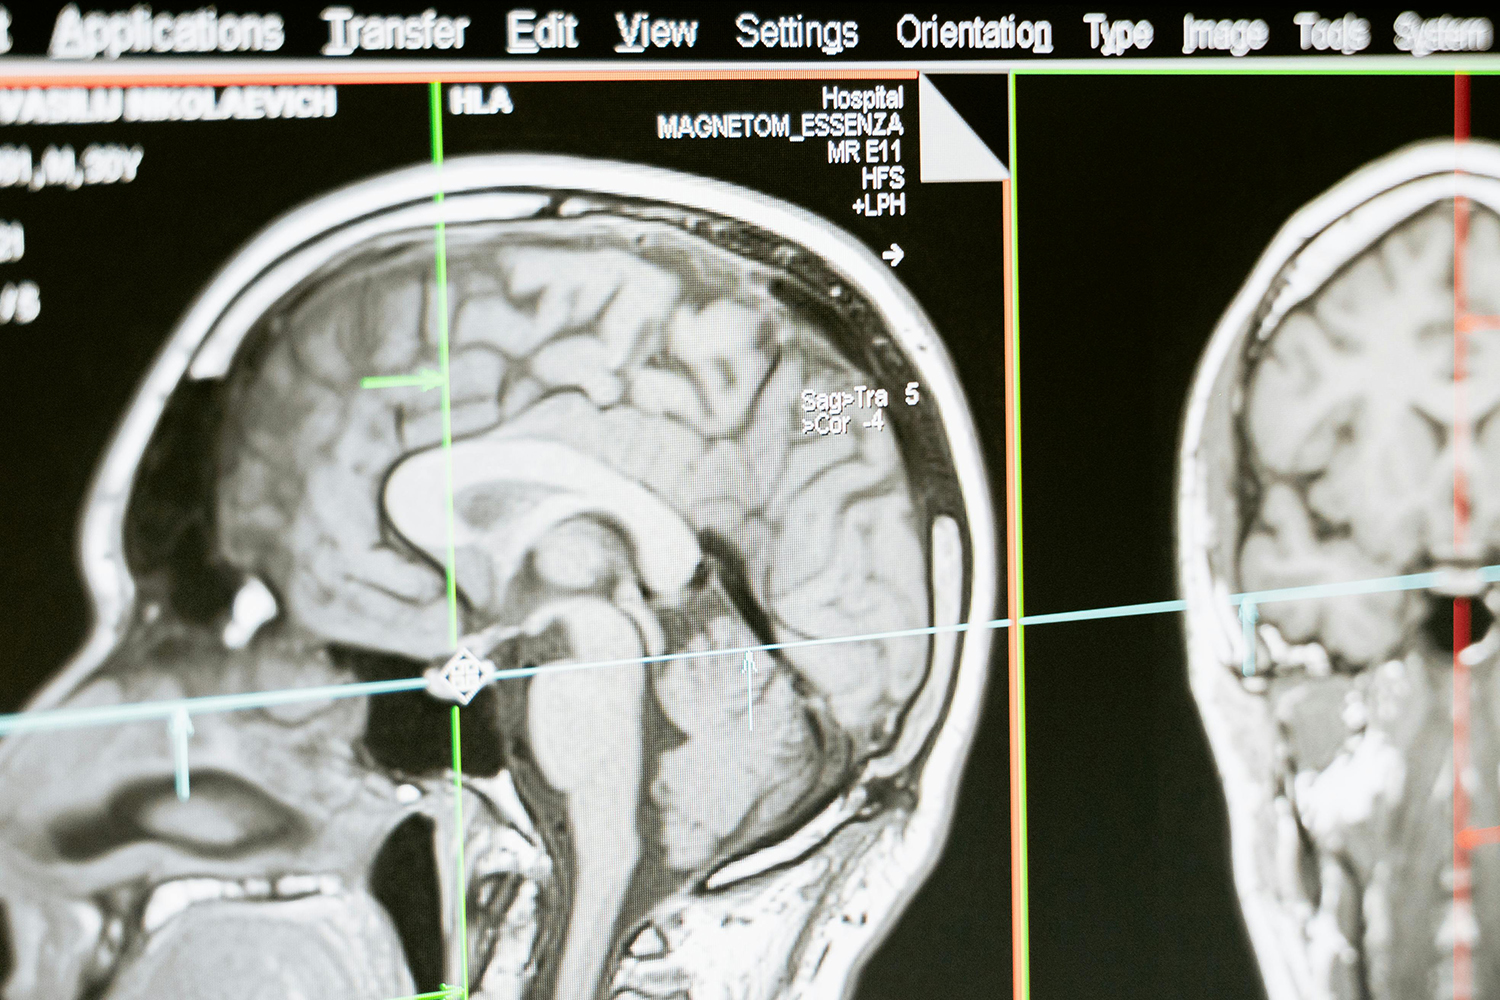

磁共振(MR)作為一種強大的成像技術已憑借其無輻射、分辨率高(尤其針對軟組織成像)被廣泛的應用于大部分疾病的診斷。

核磁共振成像(MRI)目前普遍應用于醫(yī)學檢測成像中,具有無輻射損傷的安全性,可任意方位斷層掃描等技術靈活性,加以涵蓋質(zhì)子密度、弛豫、加權(quán)成像以及多參數(shù)特征的優(yōu)勢,已成為當代臨床診斷中最有力的檢測手段之一,然而臨床發(fā)現(xiàn)某些不同組織或腫瘤組織的弛豫時間相互重疊,導致診斷困難。

核磁共振成像因其具有無創(chuàng)、快速、高解析率、高對比度等特點,在臨床上廣為使用。特別是在腫瘤的診斷中,該技術利用病變組織和正常組織物理特性的不同而獲得的結(jié)構(gòu)、功能影像,已經(jīng)成為原發(fā)腫瘤和腫瘤轉(zhuǎn)移早期診斷中不可或缺的重要依據(jù)。